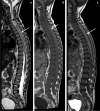

Tuberculosis (TB) remains one of the major public health threats worldwide, despite improved diagnostic and therapeutic methods. Tuberculosis is one of the main causes of infectious disease in the chest and is associated with substantial morbidity and mortality in paediatric populations, particularly in low- and middle-income countries. Due to the difficulty in obtaining microbiological confirmation of pulmonary TB in children, diagnosis often relies on a combination of clinical and radiological findings. The early diagnosis of central nervous system TB is challenging with presumptive diagnosis heavily reliant on imaging. Brain infection can present as a diffuse exudative basal leptomeningitis or as localised disease (tuberculoma, abscess, cerebritis). Spinal TB may present as radiculomyelitis, spinal tuberculoma or abscess or epidural phlegmon. Musculoskeletal manifestation accounts for 10% of extrapulmonary presentations but is easily overlooked with its insidious clinical course and non-specific imaging findings. Common musculoskeletal manifestations of TB include spondylitis, arthritis and osteomyelitis, while tenosynovitis and bursitis are less common. Abdominal TB presents with a triad of pain, fever and weight loss. Abdominal TB may occur in various forms, as tuberculous lymphadenopathy or peritoneal, gastrointestinal or visceral TB. Chest radiographs should be performed, as approximately 15% to 25% of children with abdominal TB have concomitant pulmonary infection. Urogenital TB is rare in children. This article will review the classic radiological findings in childhood TB in each of the major systems in order of clinical prevalence, namely chest, central nervous system, spine, musculoskeletal, abdomen and genitourinary system.